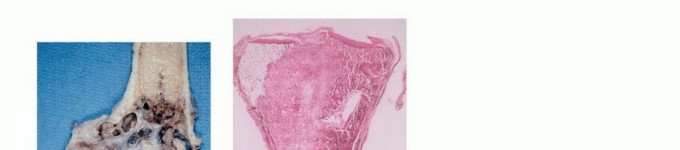

Sarcomas typically form a solid, expansile mass that grows centrifugally. Due to this centrifugal growth pattern, the periphery of the lesion is the least mature, most cellular, and most biologically active region, making it the ideal target for biopsy sampling. Unlike the true capsule that surrounds benign lesions—which is composed of compressed normal cells and mature fibrous tissue—sarcomas are generally enclosed by a reactive zone commonly referred to as a "pseudocapsule."

This pseudocapsule consists of compressed tumor cells, a fibrovascular zone of reactive tissue, and a variable inflammatory component that interacts with the surrounding normal tissues. Crucially, the pseudocapsule is not a true anatomic barrier. Microscopic tumor extensions, known as satellite lesions, frequently penetrate this reactive zone and reside in the immediately adjacent normal-appearing tissue. Therefore, a biopsy that breaches the pseudocapsule inevitably contaminates the surrounding tissue planes with malignant cells.

- Sampling: The sample must be taken from the periphery of the tumor (the most viable tissue), avoiding the necrotic center. Frozen section should be utilized to confirm that diagnostic tissue (not just necrotic debris) has been obtained.